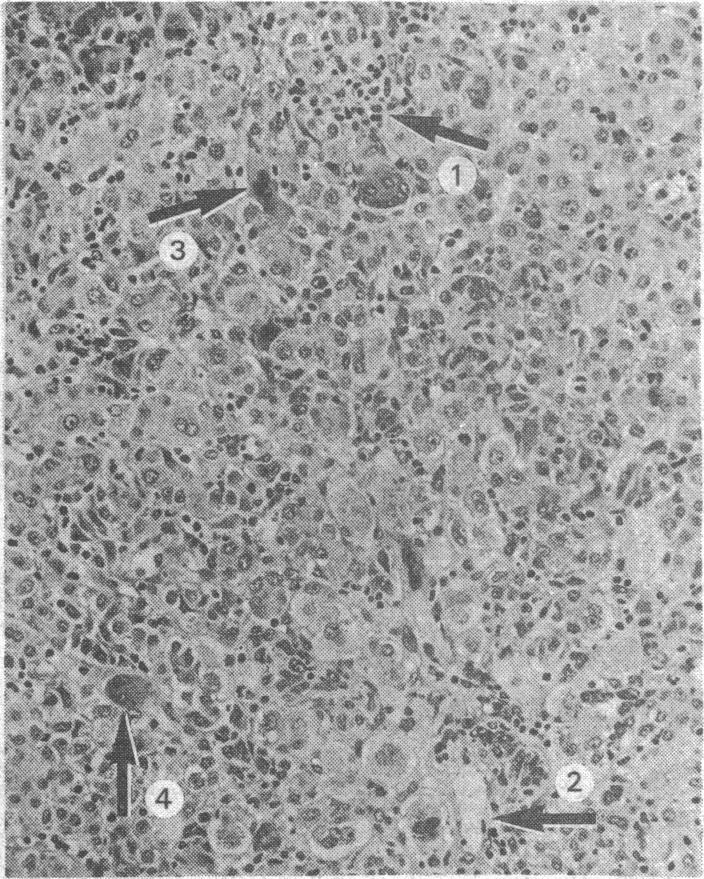

Misuse of ecstasy.

BMJ. 1992 Aug 1;305(6848):309. doi: 10.1136/bmj.305.6848.309.

Acute liver damage and ecstasy ingestion.急性肝损伤与摇头丸摄入。

Pathology of deaths associated with "ecstasy" and "eve" misuse.与滥用“摇头丸”和“伊芙”相关的死亡病理学。